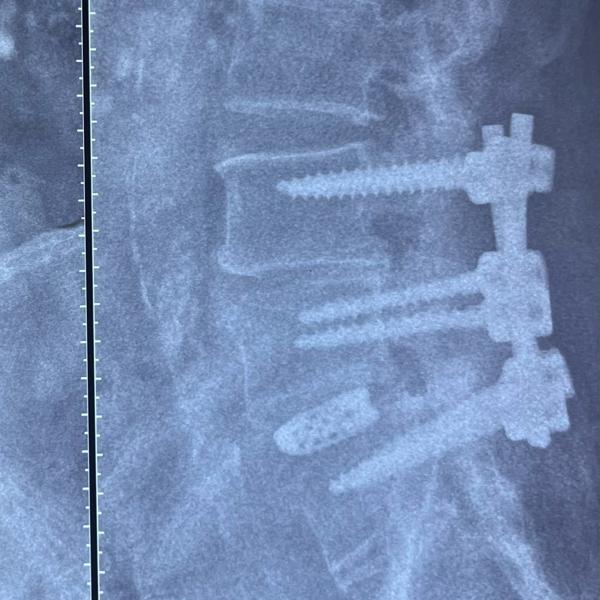

Three column fracture in a case of DISH - Pedicle...

Revision Spine Suregry - Spinal Fusion 23 year ol...